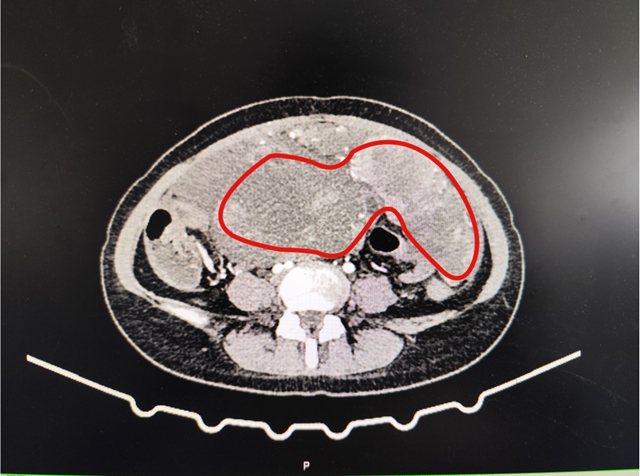

为了让小敏得到及时诊治,家人带着她到西南医科大学附属中医医院就诊。门诊完善肿瘤标志物检查后,结果提示CA125高达175.00IU/ml(远超正常范围);妇科彩超进一步显示,盆腔内有巨大实性肿物,且存在盆腔积液。进一步检查发现,肿瘤最大直径接近20CM,且并非单一肿物,整个腹腔内都布满了肿瘤。结合腹部增强CT检查,考虑恶性肿瘤性病变的可能性较大。

圈出部分为肿瘤区域